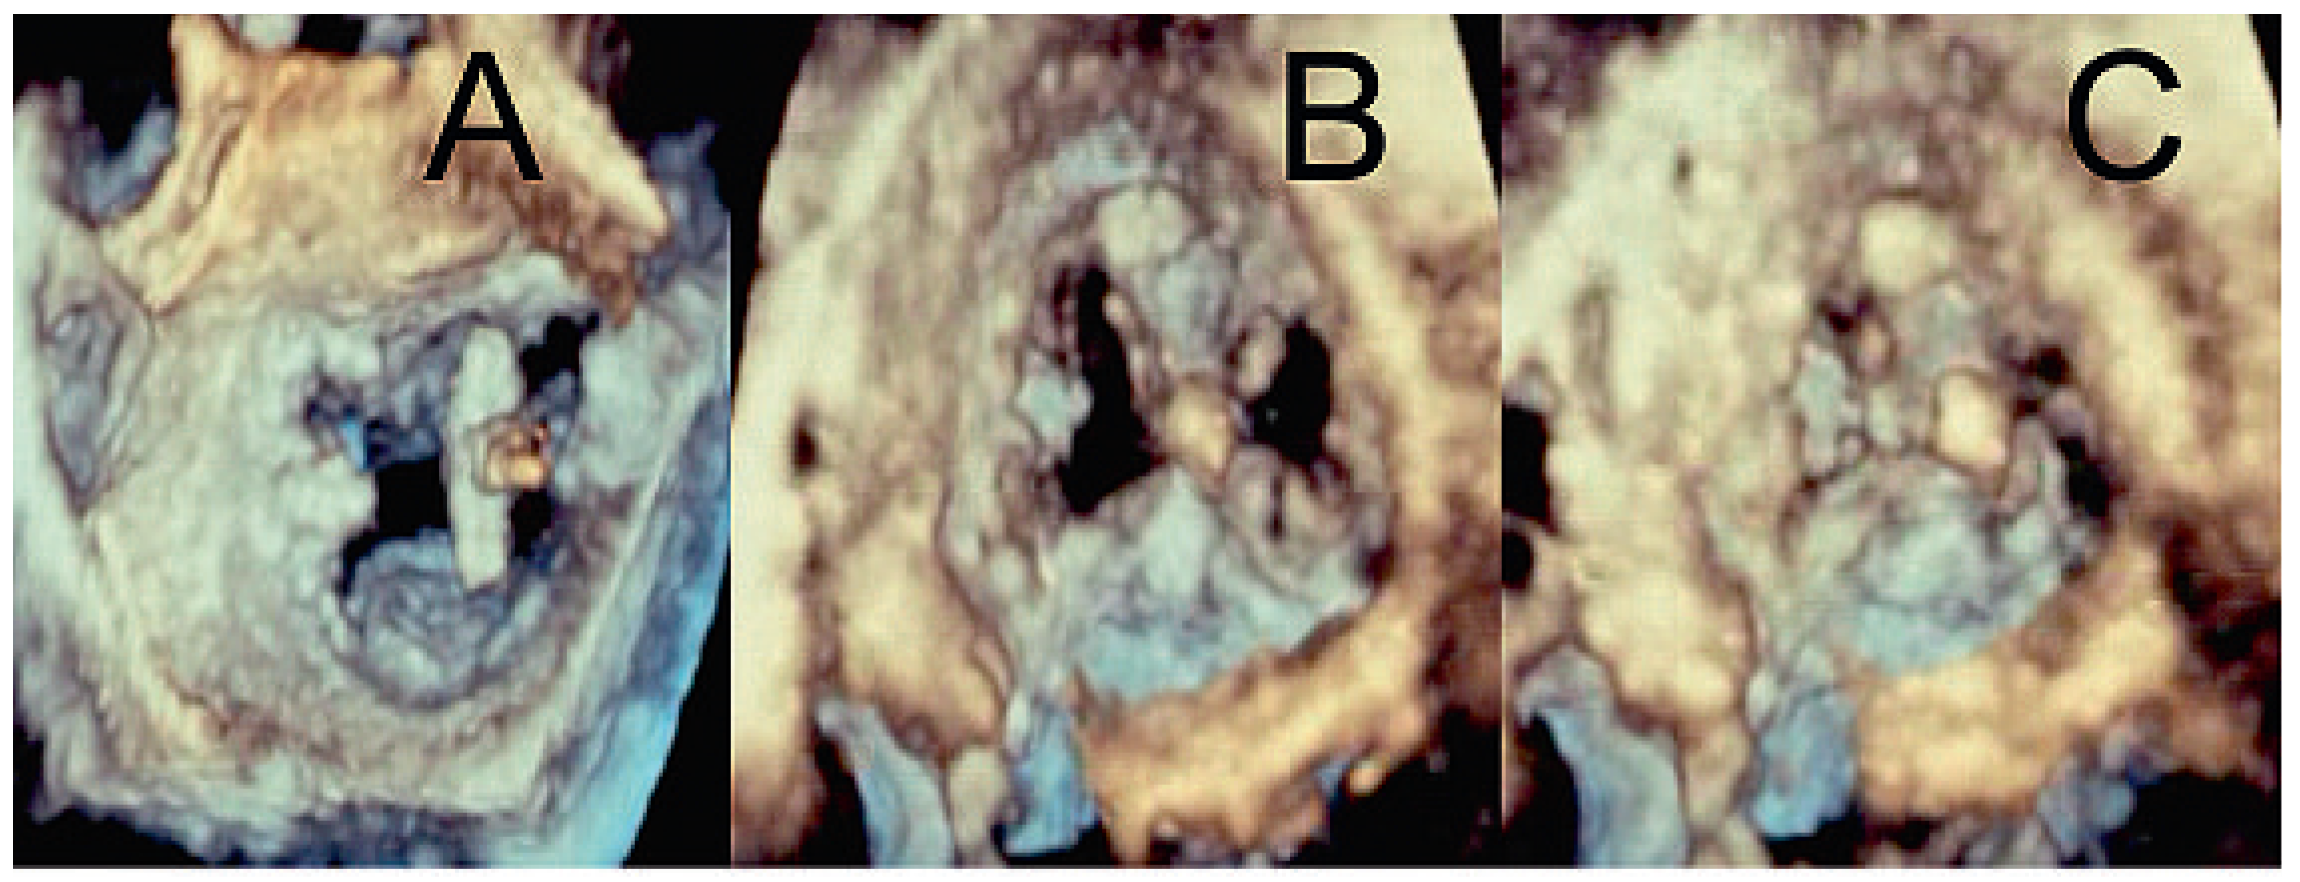

After gaining access through an 8 french sheath via the right femoral vein, transseptal puncture was performed under TEE and fluoroscopic-guidance, and an Amplatz-Super-Stiff® catheter was advanced into the left atrium (fig. 3A–C). Changing to a MitraClip-guide catheter, the clip delivery system was advanced via the left atrium (fig. 3D) into mitral position (fig. 3E). The system allows repositioning of the device under echocardiographic control until optimal placement has been found. This meant, before releasing the Clip (fig. 3F), that it could be repositioned until echocardiographic control showed the correct position of the device with mild residual regurgitation (fig. 4). 3-dimensional echocardiographic reconstruction images allowed the positioning and adjusting of the clip (fig. 5A) and the open and closed mitral valve after MitraClip® placement (fig. 5B and 5C) to be seen. The patient could be extubated in the catheter lab directly after clip implantation. The in-hospital recovery was uneventful and the patient could be discharged home three days after the intervention. During her four-week follow-up, the patient was in excellent health and reported a substantial improvement of her symptoms, reducing her exertional dyspnoea symptoms down to NYHA I–II. Echocardiographic control showed the MitraClip® in an optimal place with a residual mild-moderate regurgitation jet. On the chest x-ray film, the metallic clip can easily be identified (fig. 6).

Figure 5. Three-dimensional echocardiogram showing the MitraClip® from the left atrium (A). Open (B) and closed (C) mitral valve after release of the device.